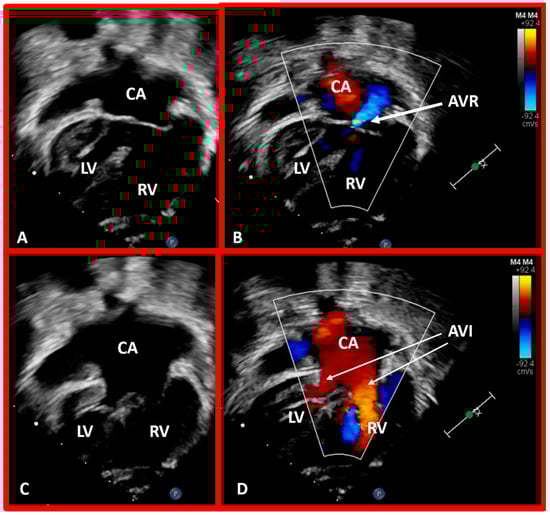

5.4. What Is the Status of Atrioventricular Connections?

Figure 44. Selected echo frames in apical four-chamber views of a patient with dextrocardia and ventricular inversion demonstrating the connection of the common atrium (CA) with both ventricles via a common atrioventricular valve. The common atrioventricular valve is completely closed in (A,B), whereas it is open in (C,D). Atrioventricular valve regurgitation (AVR) is shown in (B) with a thick arrow. Atrioventricular inflow (AVI) is marked with thin arrows in (D). Left ventricle (LV) and right ventricle (RV) are labeled.